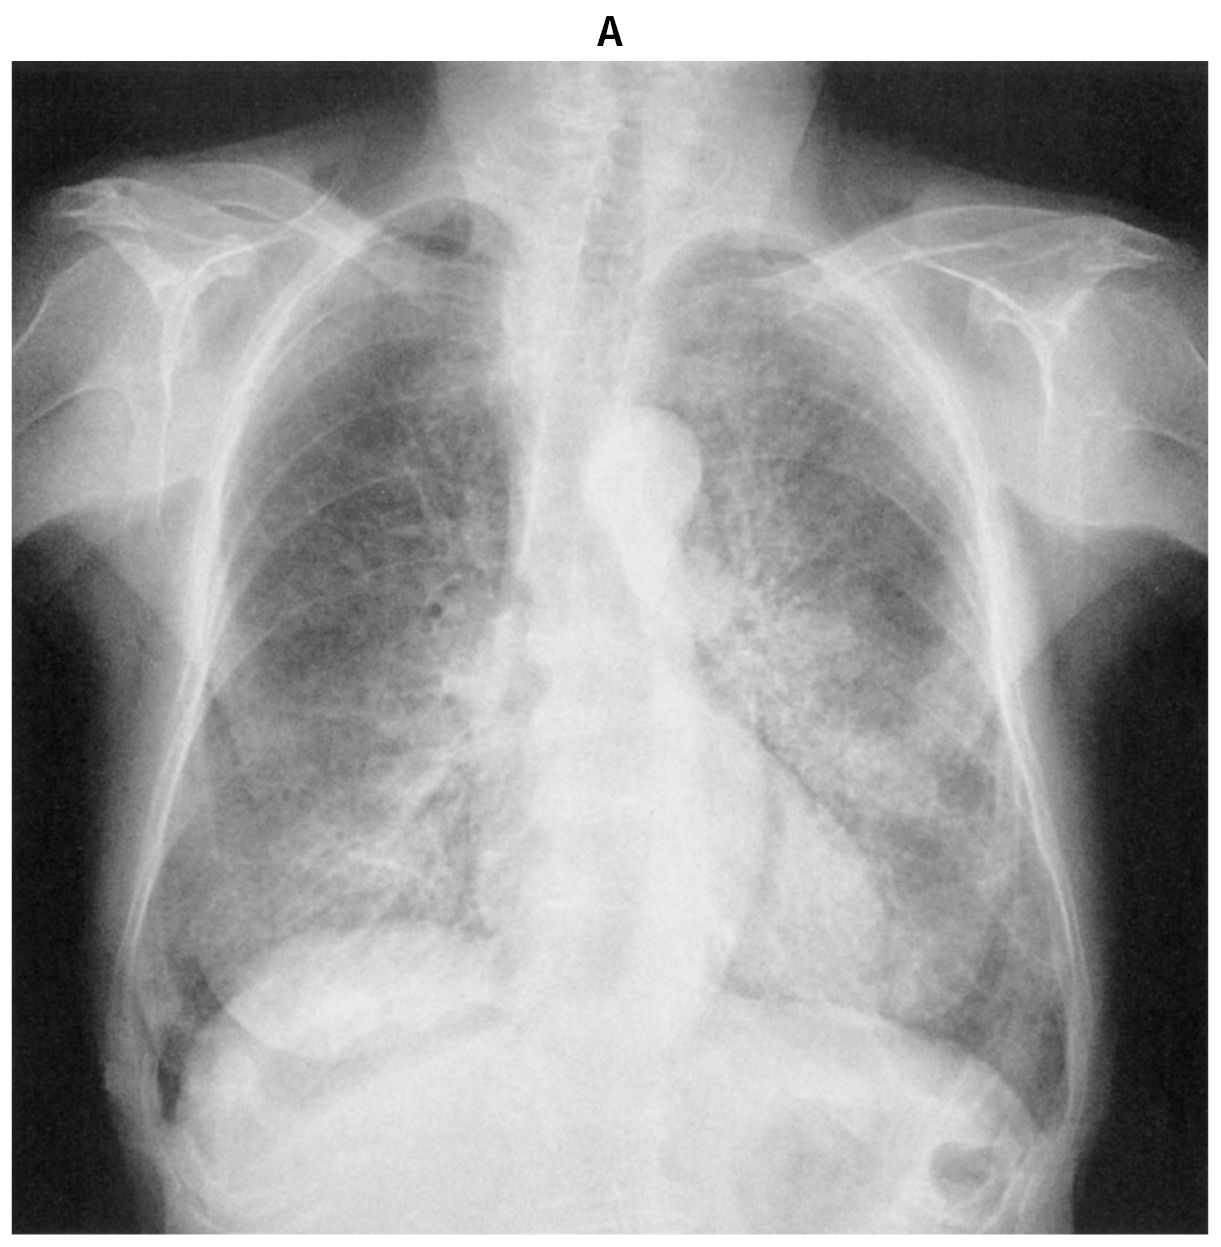

78歳の女性。労作時の息切れを主訴に来院した。6か月前から咳嗽を自覚し,1か月前から労作時の息切れが出現した。体温36.5℃。脈拍92/分,整。血圧136/90mmHg。呼吸数20/分。SpO2 92%(room air)。両側下肺野にfine cracklesを聴取する。血液所見:赤血球467万,Hb 13.8g/dL,Ht 41%,白血球3,800,血小板32万。CRP 0.1mg/dL。胸部エックス線写真(A),胸部単純CT(B)及び気管支肺胞洗浄液の写真(C)を下に示す。

無料会員登録していただくと、実際の解説をすべて見ることができます。急性の呼吸困難を主訴とする疾患としては,喉頭浮腫,気道異物,自然気胸,気管支喘息,慢性閉塞性肺疾患の急性増悪などの呼吸器疾患,心不全(急性,慢性の急性増悪),肺血栓塞栓症などの循環器疾患が代表的である。この症例では呼吸器感染症と心不全が疑われるが,胸部エックス線写真は肺炎像というよりも両心不全を示唆する所見を示している。診断:心不全(両心不全)(Nohria分類wet and warm) 選択肢考察 ×a 強い呼吸困難,胸痛などにより安静が保てない場合には,血管拡張による前負荷軽減と,交感神経抑制による心筋酸素消費量の減少を目的としてモルヒネを使用する。この症例ではモルヒネが必要となるほどの興奮状態ではない。